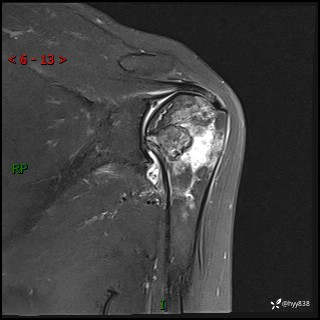

肱骨正侧位片

肱骨MRI平扫(axi T1WI+cor T2WI-fs)+CE-fs(COR+SAG)